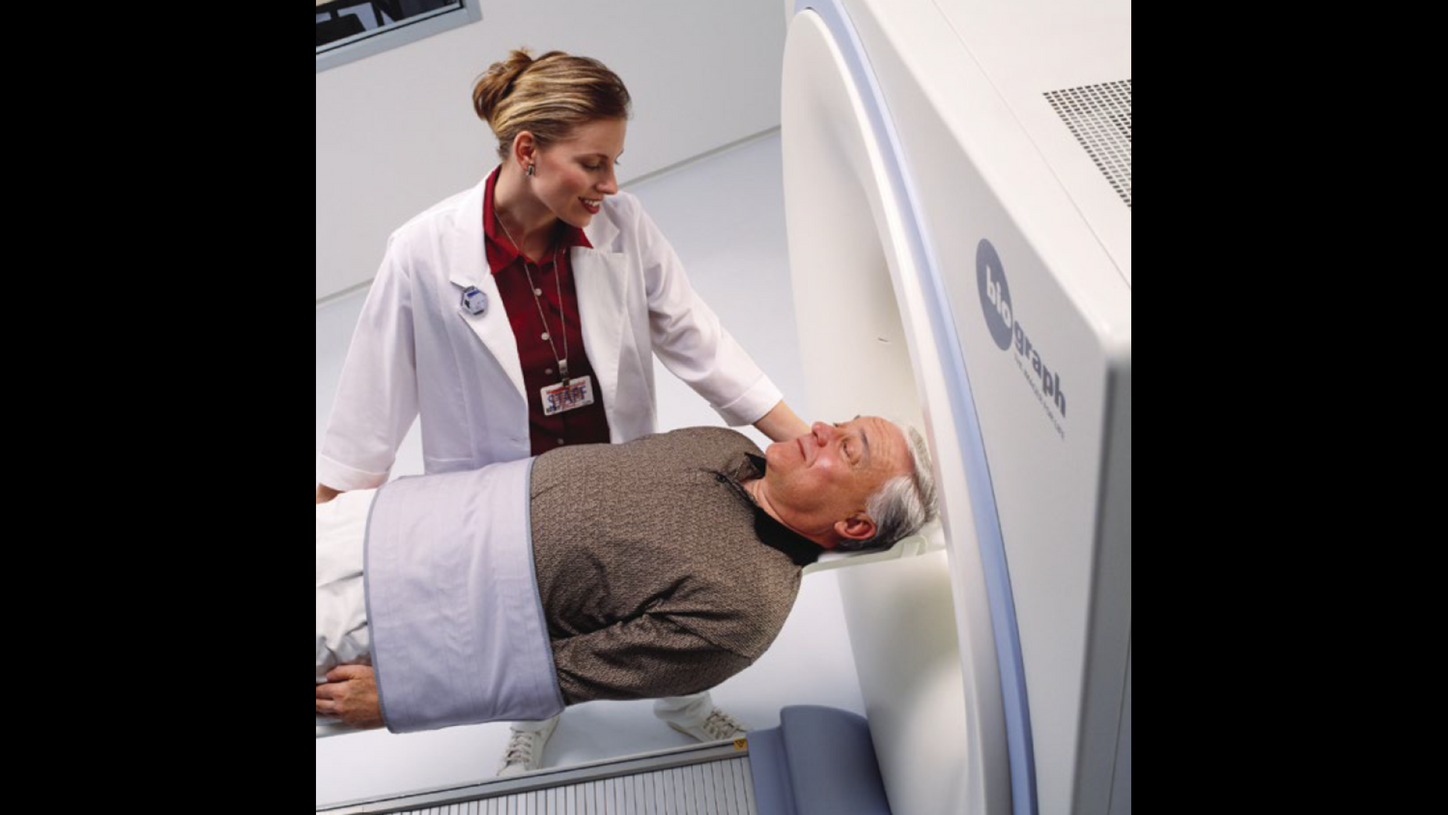

While surgeons and oncologists were generally more receptive to the idea, the wider medical community’s initial reaction to the new PET/CT scanner was, at best, uncertain. Why? Because it was hybrid technology that did not quite fit. Was it nuclear medicine? Was it radiology? No one knew exactly where it belonged. And would it require two technologists to operate it? Two physicians to read the scans? Many questions were asked.

The co-inventors, Townsend and Nutt, and members of the team remained involved in PET/CT’s development. In November 2000, the new scanner was unveiled to the world at the Radiological Society of North America’s (RSNA) annual meeting in Chicago, Illinois, USA. In December of the same year, the PET/ CT concept and prototype design was honored by TIME magazine as “Medical Invention of the Year.”1 By mid-2001, the first commercially available Siemens Biograph PET/CT system was installed at the University of Pittsburgh.

Full circle: from pioneer to patient

Last year, Townsend himself

underwent a PET/CT scan following

the discovery of a suspicious nodule

in his left lung. The PET/CT was

consistent with an adenocarcinoma

that was confirmed by biopsy.

Fortunately, it was an early stage 1

tumor that was removed surgically

and a 6-month follow-up scan showed

no evidence of disease. Reflecting on

his own patient experience, Townsend

recalled that the imaging team who

performed the scan at the University

of British Columbia Cancer Centre,

Vancouver, Canada, were aware of

Townsend‘s background. The

technologist who gave him the

injection of FDG quipped, “‘I guess I

don’t need to explain the imaging

procedure to you, do I?‘” remembers

Townsend, with a smile.